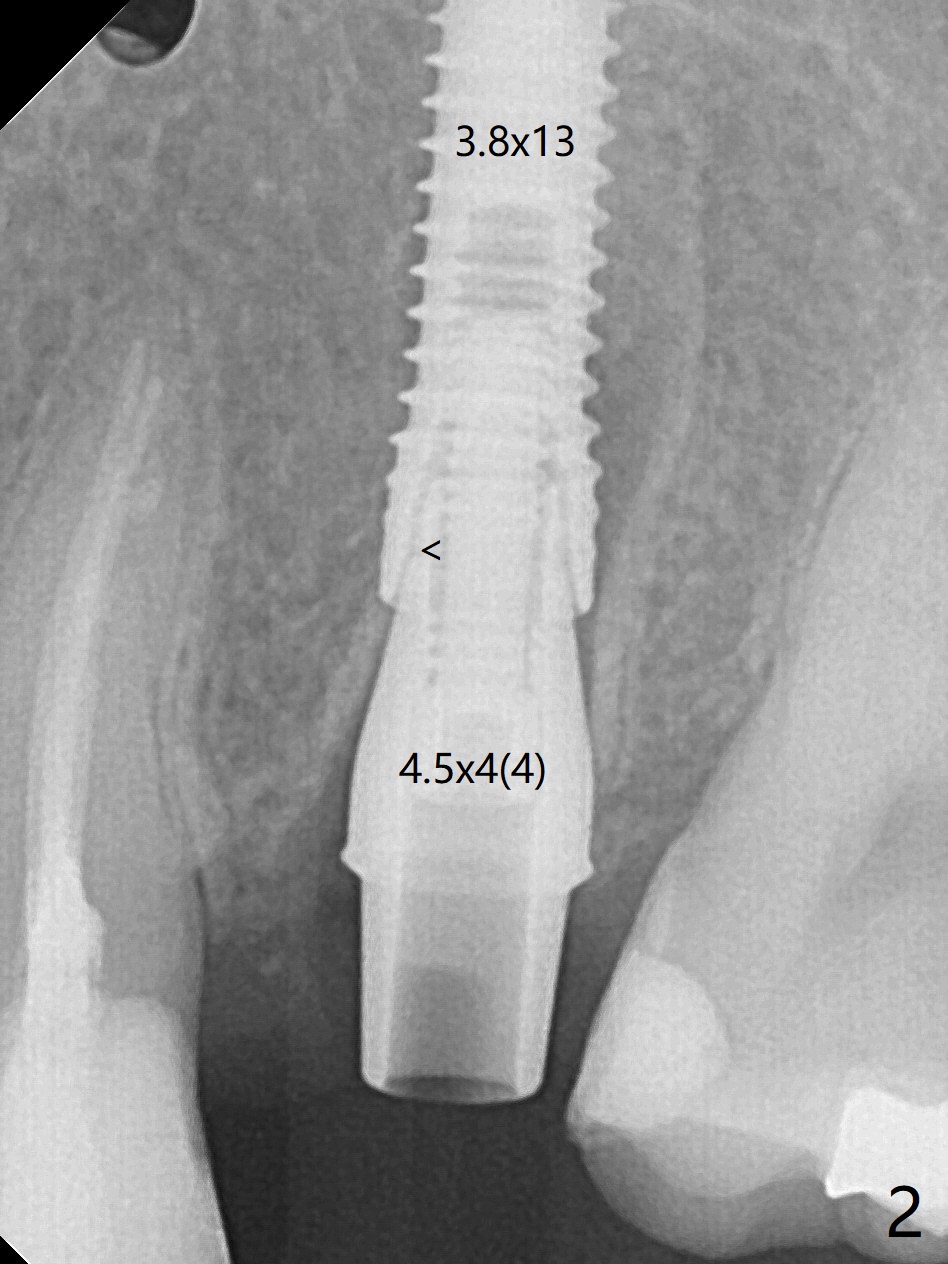

要植入13或者15毫米植体一直犹豫不决,最后植入前者,扭力低,以致放置基台时,植体随之旋入(图二)。最后只好去除基台,用手指倒退植体,放置皮质骨粉(图三:C(密度特别高)),胶原塞以及6个月吸收膜,缝合,牙周敷料。